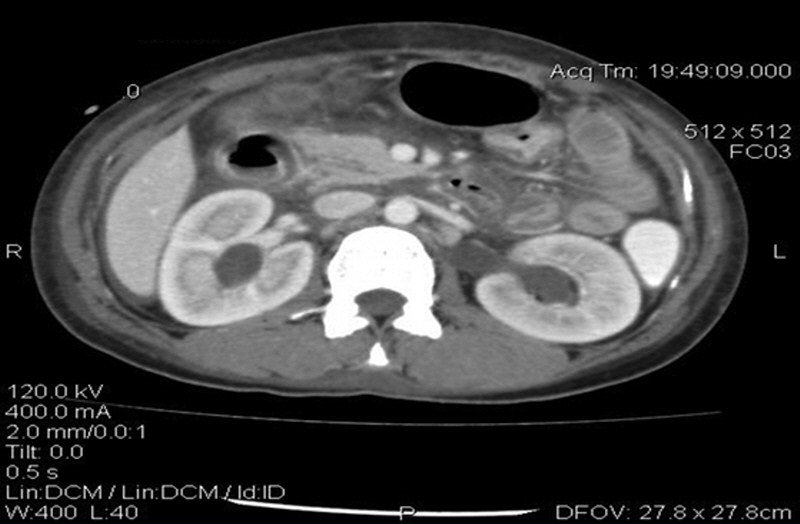

腹膜结核,结核结节

肠,腹膜结核高清内镜病例涂片

结核性腹膜炎的诊断现状课件ppt

腹膜透析相关结核性腹膜炎1例

腹水且有结核病史,这次真不是结核性腹膜炎